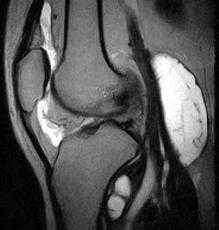

По данным УЗИ коленного сустава: признаки кисты заднего отдела коленного сустава размером 9*5*3 см. По данным МРТ коленного сустава: признаки синовиальной кисты заднего отдела сустава размером 8,5*4,5*3 см, дегенеративного комбинированного разрыва внутреннего мениска и хондромаляции (размягчения хряща) III степени.

МРТ коленного сустава позволяет видеть все камеры (карманы) капсулы коленного сустава. А также – сопутствующие изменения в колене, которые могут имет отношение к кисте Бейкера.

Важным этапом диагностики при кисте Бейкера является выявление причины воспаления синовиальной оболочки колена. Это ключевой вопрос. Он позволяет решить проблему кардинально, вылечить кисту Бейкера без операции. И больше к этой проблеме не возвращаться.